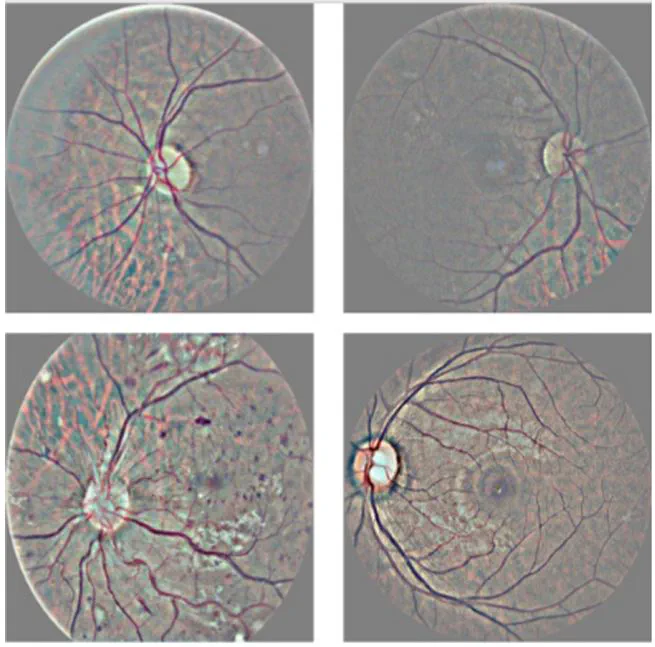

Diabetic retinopathy is one of the leading causes of blindness. Its damage is associated with the deterioration of blood vessels in retina. Progression of visual impairment may be cushioned or prevented if detected early, but diabetic retinopathy does not present symptoms prior to progressive loss of vision, and its late detection results in irreversible damages. Manual diagnosis is performed on retinal fundus images and requires experienced clinicians to detect and quantify the importance of several small details which makes this an exhaustive and time-consuming task. In this work, we attempt to develop a computer-assisted tool to classify medical images of the retina in order to diagnose diabetic retinopathy quickly and accurately. A neural network, with CNN architecture, identifies exudates, micro-aneurysms and hemorrhages in the retina image, by training with labeled samples provided by EyePACS, a free platform for retinopathy detection. The database consists of 35126 high-resolution retinal images taken under a variety of conditions. After training, the network shows a specificity of 93.65% and an accuracy of 83.68% on validation process.